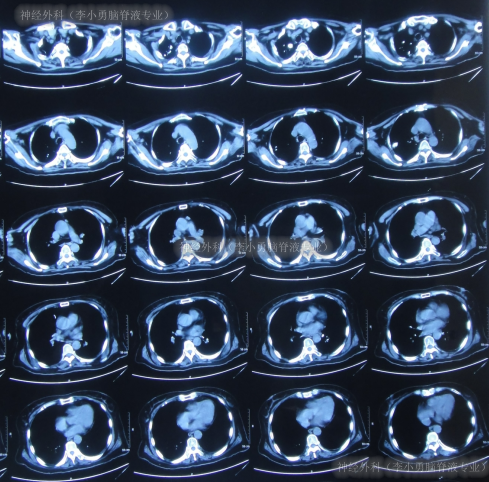

第2家医院出院1月余即2012年2月7日,夜里起夜突然又重复发作以前的症状(恶心呕吐、头昏),且比前2次发作严重,2012年2月8日住入第3家医院:呼和浩特市某三甲医院的神经外科治疗,入院查头颅CT(图-2)和MRI(图-3);脊髓核磁(图-4);肺部CT(图-5)及多次腰椎穿刺脑脊液化验检查(糖低、蛋白高),诊断为:结核性脑膜炎,脑积水。

图-5:2012年2月9日肺部CT